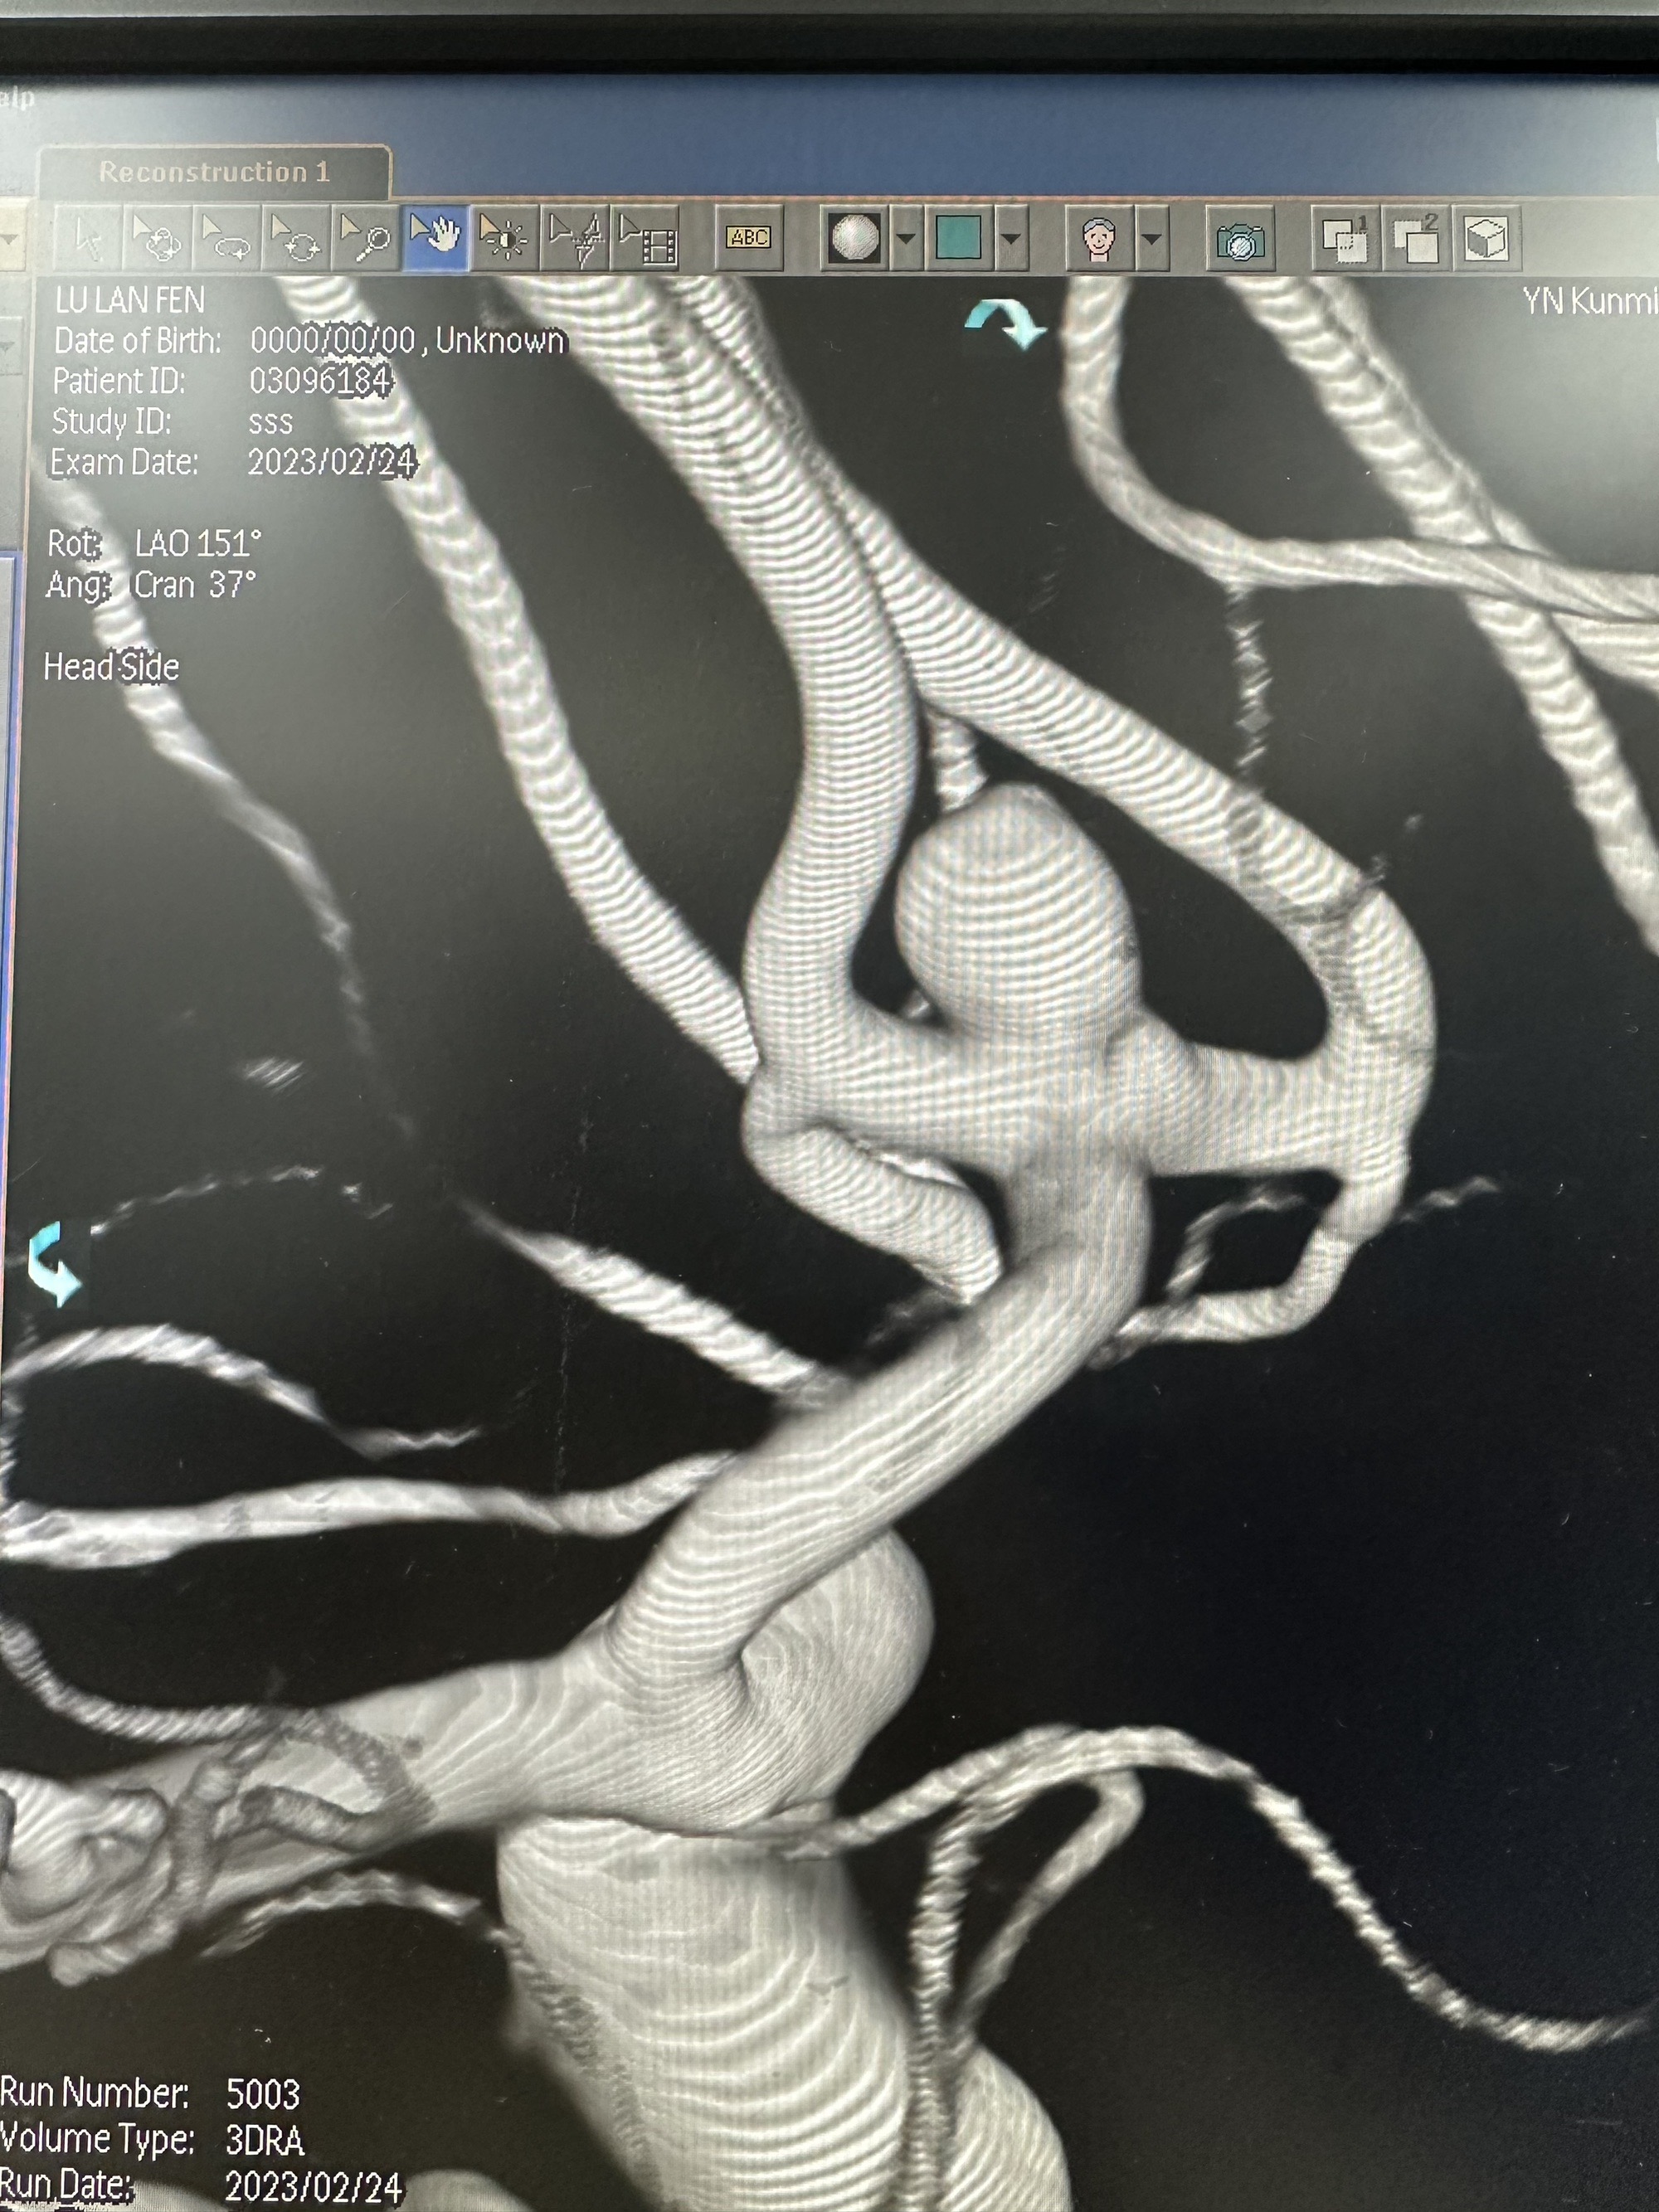

3D造影

另外一个角度